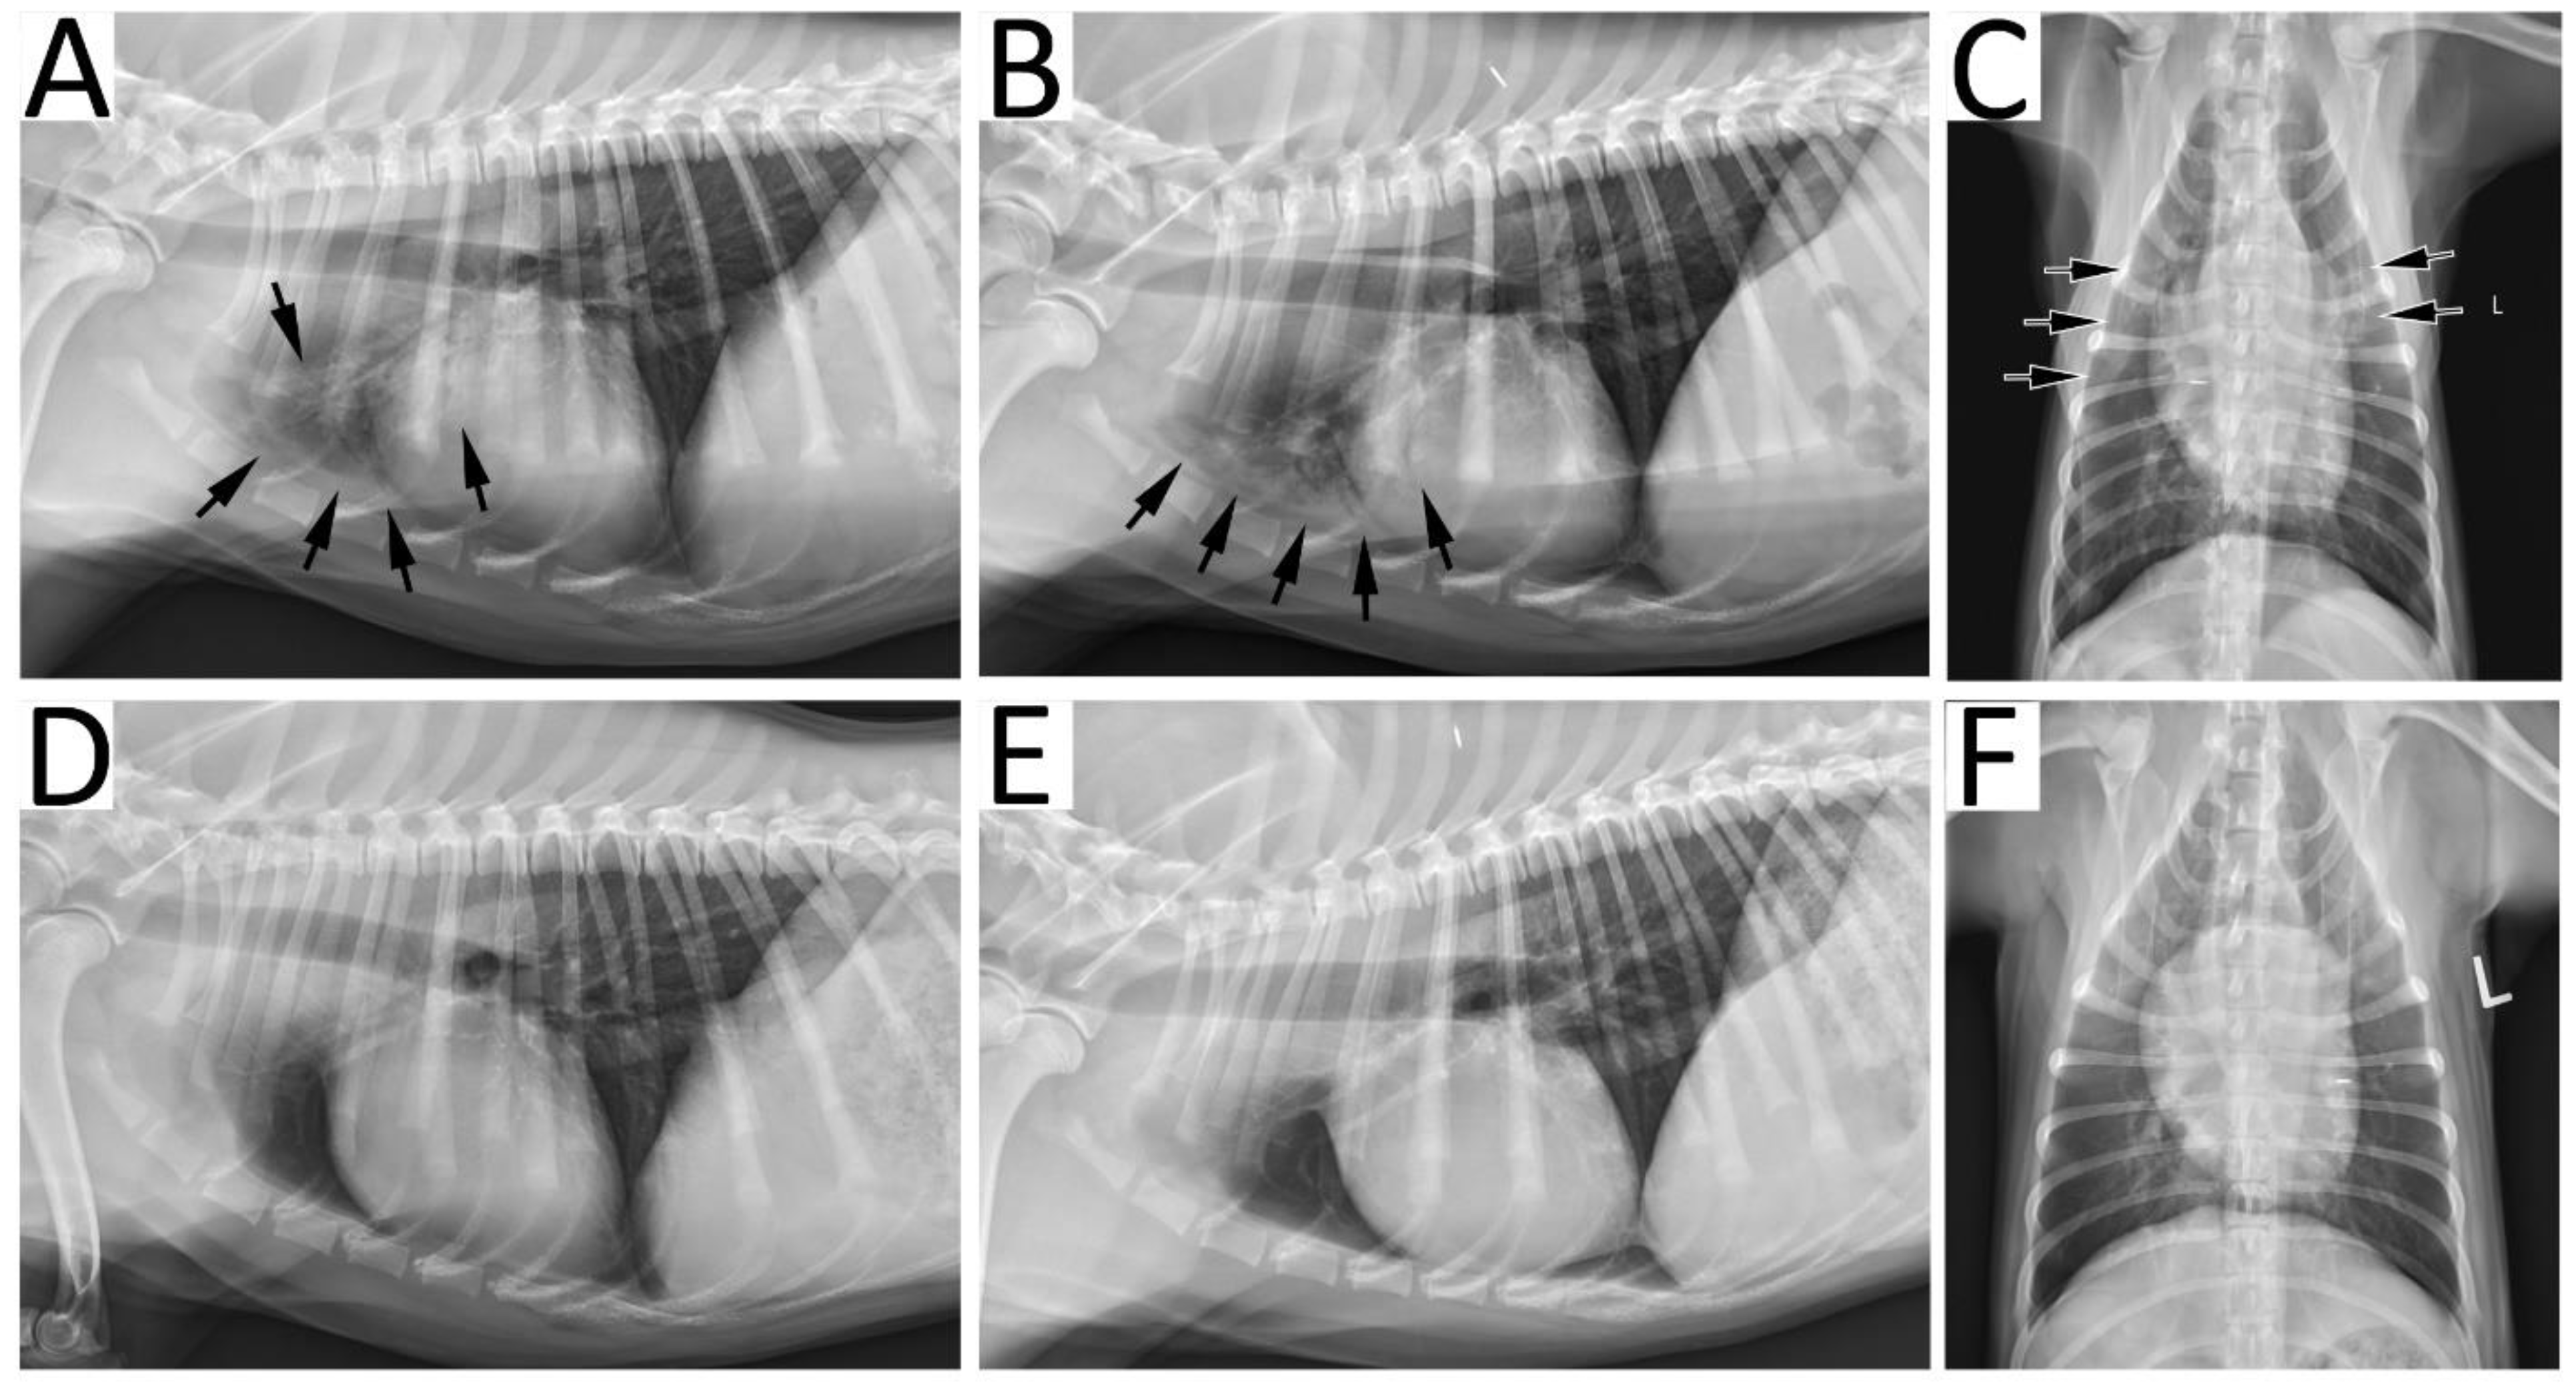

Radiographic resolution: Based on the GRS there was no significant difference in the severity of radiographic lesions at each of the time points between the two treatment groups (p > 0.05). Overall, there was a significant decrease in the GRS over time regardless of the group (p < 0.0001). In the A10 group, there was a significant overall decrease in the GRS at each follow-up visit compared to baseline (p < 0.05). However, one of the dogs had a resolution of radiographic findings at the first visit (GRS = 1), and despite lacking an identified predisposing condition, there was evidence of re-aspiration at the second visit (GRS = 3). This dog did not have a second BAL but was treated with nebulization and coupage without antimicrobials and on the third visit had a GRS of 2. In the A21 group, there was no significant difference in the GRS between the baseline and the first follow-up visit (p = 0.532), but there was a significant decrease at the second (p = 0.012) and third visit (p = 0.003). Despite clinical and hematologic resolution of pneumonia, by the final study visit at day 60, 3/8 dogs had persistent radiographic lesions; two dogs in the A10 group had a final GRS of 2, and one dog in the A21 group had a final GRS of 3. Figure 2 provides an example of radiographic resolution of pneumonia.

Figure 2.

Radiographic resolution of bacterial pneumonia in a 9-month-old male neutered Golden Retriever dog. At initial presentation, right lateral (A), left lateral (B) and ventrodorsal (C) recumbent radiographic projections demonstrated an alveolar pattern (arrows) in the cranial lung fields characterized by increased opacification, air bronchograms and indistinct pulmonary vasculature. Since both the cranial segment of the left cranial lung lobe and right cranial lung lobe were affected, a global radiographic score of 4 was assigned, corresponding to multifocal consolidation. After a full course of therapy, right lateral (D), left lateral (E) and ventrodorsal (F) recumbent projections show resolution of lung lesions and thus, a global radiographic score of 1 was given.